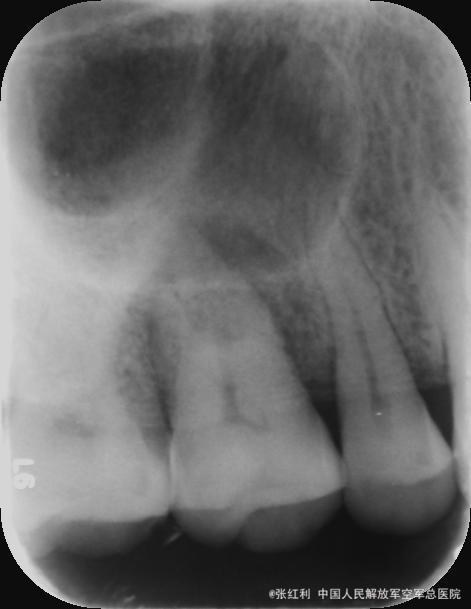

检查:16牙冠完整,牙龈红肿,腭侧可见一窦道,PD=13-5mm,叩痛(++),松动II度。 X线示:16髓腔部分钙化,根管影像不清晰,未见根充影像,根尖周大面积低密度影,近远中根周膜增宽。

诊断:16牙周牙髓联合病变(逆行性牙髓炎) 治疗计划:16RCT+牙周基础治疗+改良翻瓣术 初诊:常规局麻下开髓揭顶,髓腔钙化,少量髓石,超声探查根管,拔髓,根管较细,疏通,封EDTA,一周后复诊。 复诊1:去暂封,继续探查根管,P、MB通畅,DB根尖区钙化,电测根长:P=MB=17.5mm,DB=15mm,EDTA下手扩+机扩+protaper根备至F2,生理盐水+双氧水反复交替冲洗,干燥,CP棉球+ZOE暂封,约日复诊。 复诊216消毒,局麻下洁治,刮治,小翻瓣术,搔刮出大量肉芽组织及少量牙石,根面平整,浓替硝唑冲洗,复位,OHI,约日复诊。 复诊3:腭侧窦道基本愈合,去暂封,超声荡洗,干燥,试尖可,糊剂+热牙胶根充,棉球+ZOE暂封,2周后复诊树脂充填。 复诊4:复诊常规树脂充填,腭侧窦道愈合(忘记拍片子,太遗憾,但是患者1个月后会过来复查)。